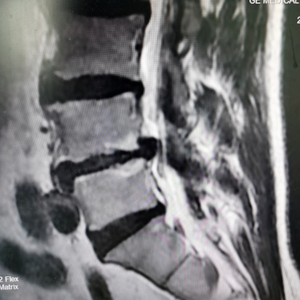

术前腰椎MRI提示:腰4/5椎间盘突出伴侧隐窝狭窄/图源 重医附三院

孙红振医生和同事为邹先生完善术前检查和评估,并组织病例分析和术前讨论,考虑患者存在腰椎间盘突出伴侧隐窝狭窄,腰椎不稳,椎间隙高度明显丢失等。若采取传统开放减压融合手术需对患者椎旁软组织进行广泛剥离,手术创伤大,手术风险高,老年患者术后恢复慢且潜在并发症多。为彻底解除神经压迫,重建脊柱稳定性,尽可能降低患者医疗费用,缩短住院及卧床时间,经与患方充分沟通,孙红振医生团队决定实施微创通道下经椎间孔入路腰4/5和腰5/骶1椎体间融合术(MIS-TLIF)。